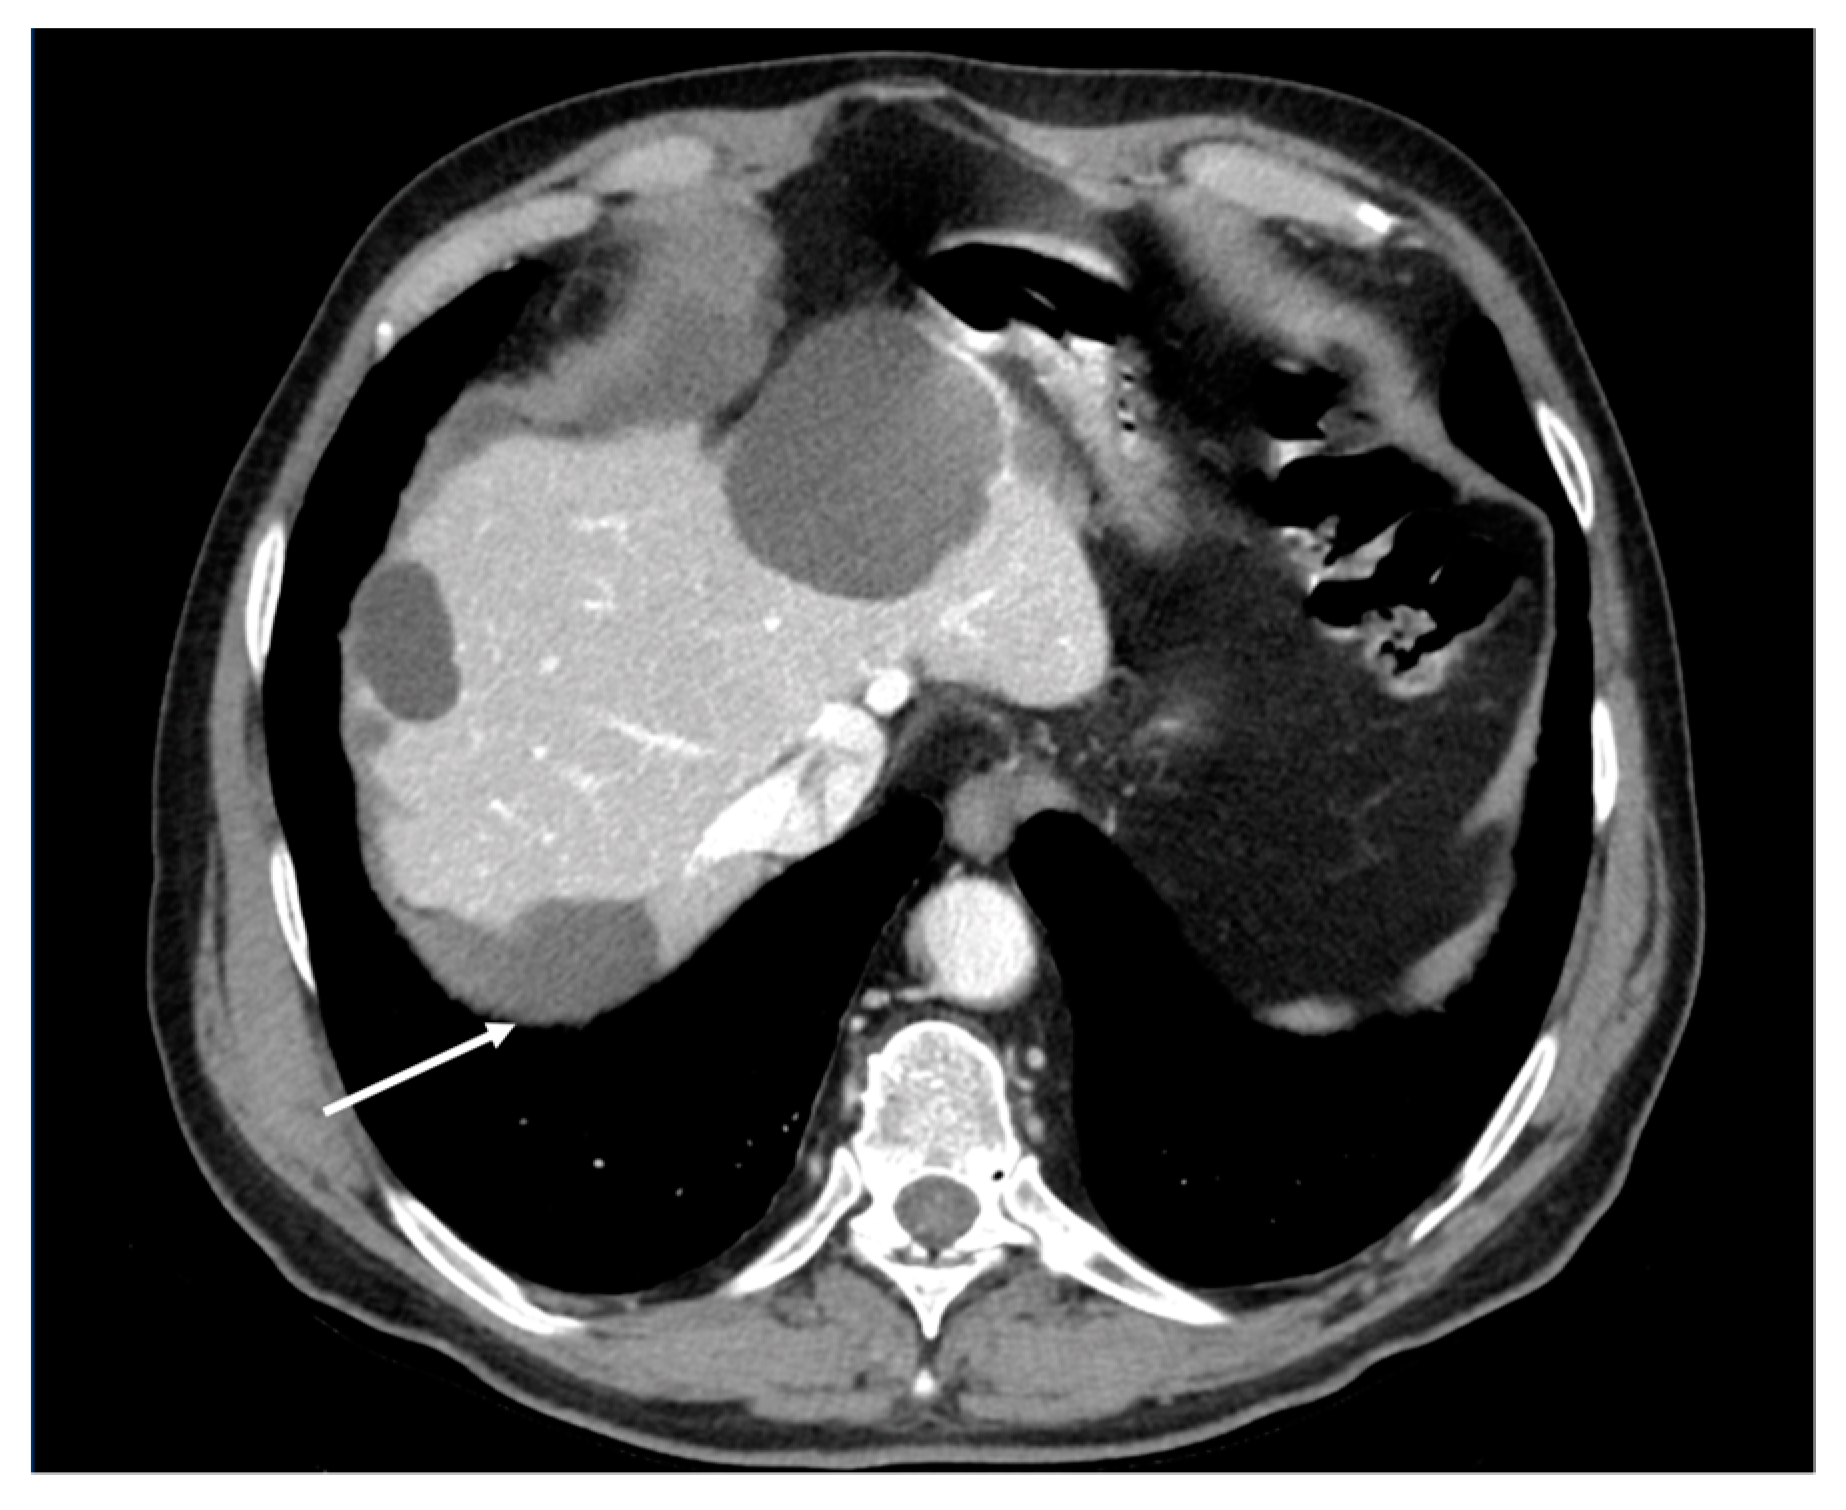

- Plaque pattern: confluent nodular tumor implants that are typically located on the lower surface of the right diaphragm and may manifest as a depression of the liver surface, mimicking capsular or subcapsular liver metastases. They present as areas of low attenuation relative to the parenchyma on postcontrast scans [94,95] (Figure 10).